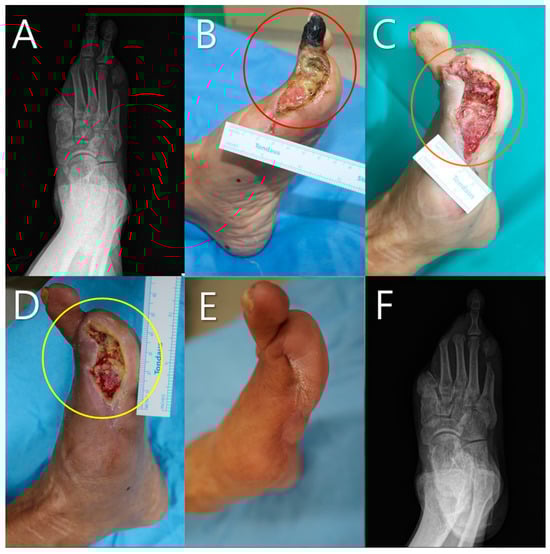

| 5 | 62 | Female | Poorly Controlled Diabetes | Right Second Toe | 20 × 20 | 1 | 6 | 10 | None | Healing without complication |